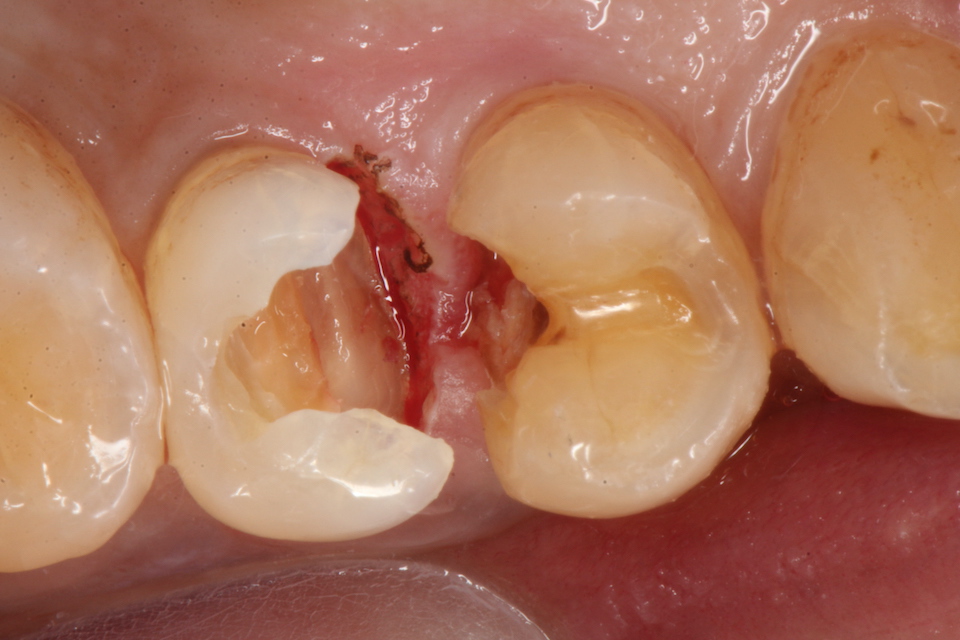

下顎7番の頬側歯茎部カリエスの原因 2025.06.04